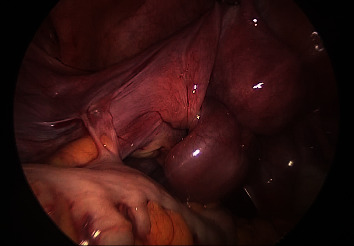

Case: A 15-year-old female patient with no history of abdominal surgery or sexual intercourse presented with acute left lower abdominal pain and purpura. MRI revealed hydrosalpinx in the left adnexal region. Her abdominal pain had completely resolved at our examination; she was followed up as an outpatient. One month after the initial presentation, she experienced a large volume of watery discharge. Magnetic resonance imaging, which was performed every three months, showed a gradual decrease in the size of the hydrosalpinx; however, it persisted in the left adnexal region. She was counseled to receive laparoscopy to treat the hydrosalpinx, which was the most likely cause of the watery discharge. IFTT was detected during the laparoscopy, and left salpingectomy was performed for pathological evaluation of the persistent hydrosalpinx. Following laparoscopy, the patient's watery discharge was resolved. Pathological findings confirmed no signs of malignancy.